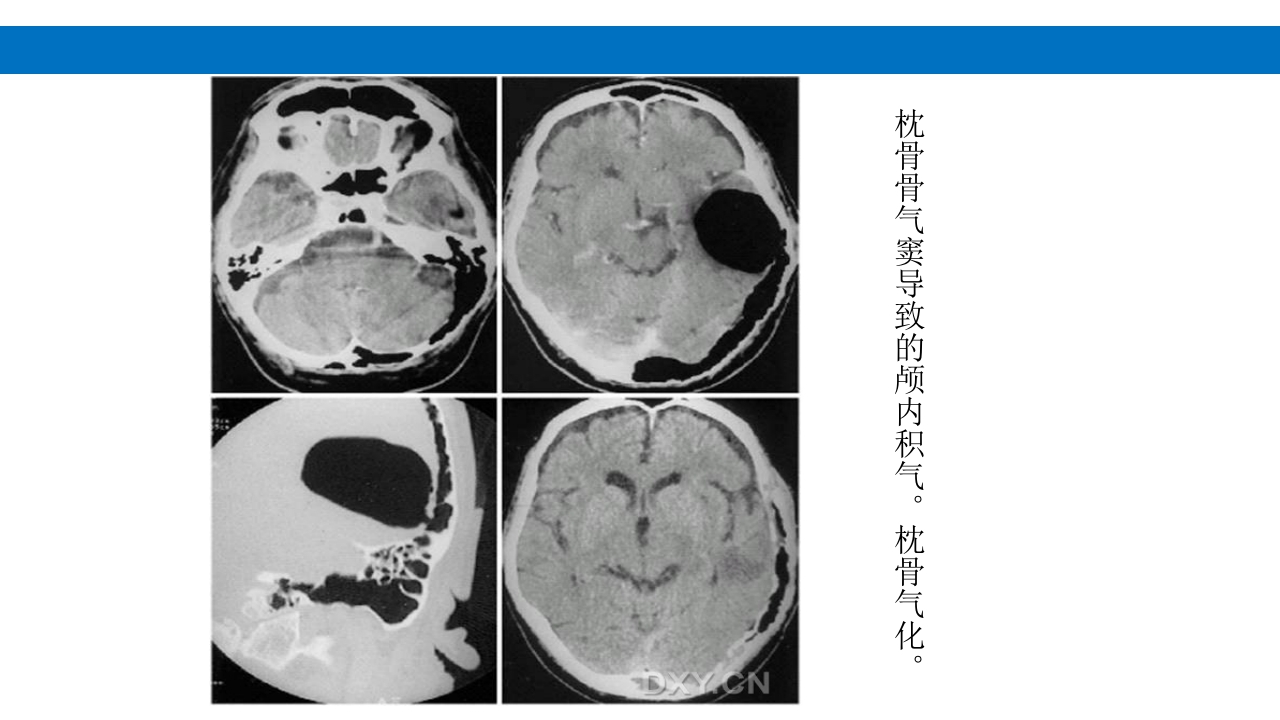

颅脑损伤的并发症及后遗症 讲解人:xxx 20XX年x月x日 1.颅骨骨髓炎 病因:为头皮软组织、中耳、乳突和副鼻窦等处炎性感染而经导 血管侵入颅骨内或颅脑开放伤感染所引起,亦可由菌血症后发生 的细菌栓子由血运转移至颅骨内。 影像学表现: 头部CT: 1.表现为不规则的蜂窝状骨质破坏区,主要位于板障,亦可累 及内外板。 2.破坏区内可见高密度的米粒状细小的高密度死骨。 3.周边可见骨质硬化增生,颅板外无骨膜反应。 4.局部的头皮可见软组织肿胀。 头部MRI: 由于受累部位细胞成分和水量增多,T1WI为低信号, T2WI为高信号,急性期边界不清,慢性期病灶局限, 边界清晰。MRI显示骨质破坏没有CT效果好。 治疗: 除应用抗菌药物控制感染外,当感染局限或已有死骨形成后, 应行手术切除感染...